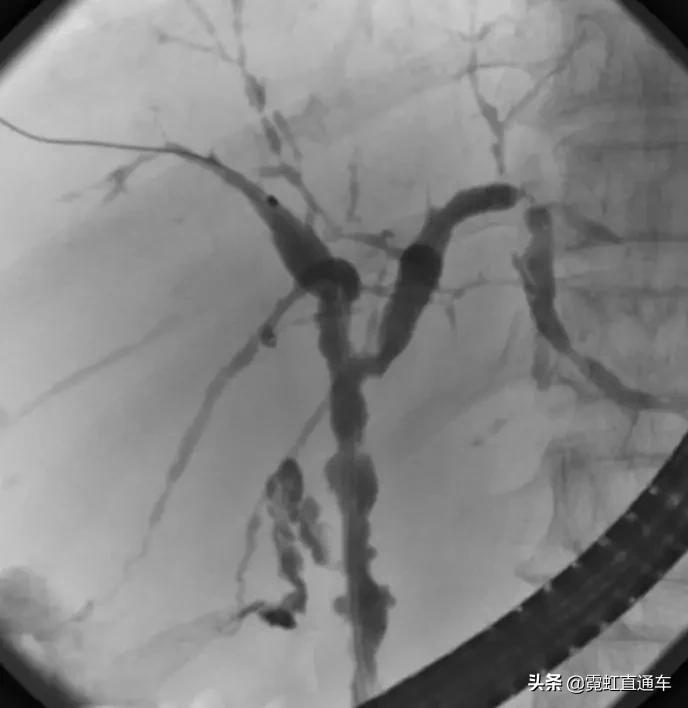

3、PSC影像学表现(日本厚生劳动省官网提供)

ERCP:胆管狭窄与扩张交互,呈串珠状改变

多发短小狭窄,胆管环状受累

PTCD:胆管呈边缘不整羽毛状

ERC:胆管壁呈憩室样突出